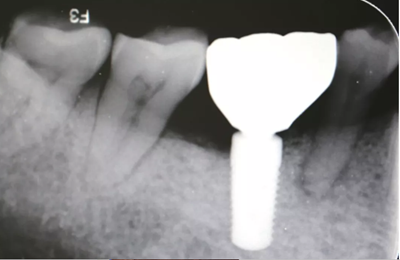

4、術(shù)前根尖片

植骨術(shù)后半年根尖片,種植體周?chē)陷^好遠(yuǎn)中少量骨吸收。

二期術(shù)后1月根尖顯示種植體周?chē)琴|(zhì)穩(wěn)定,無(wú)進(jìn)一步吸收。